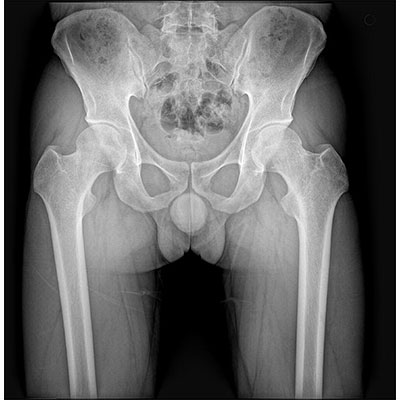

● 采用自主研發(fā)的技術(shù),在保證優(yōu)質(zhì)圖像的前提下,大大降低X射線劑量,用心呵護醫(yī)護工作者及患者的健康。

● 短曝光時間,便于老年人、兒童、殘疾人進行臨床拍攝。避免這類群體因不能有效控制身體運動等因素造成的運動偽影,提高攝片質(zhì)量及效率。